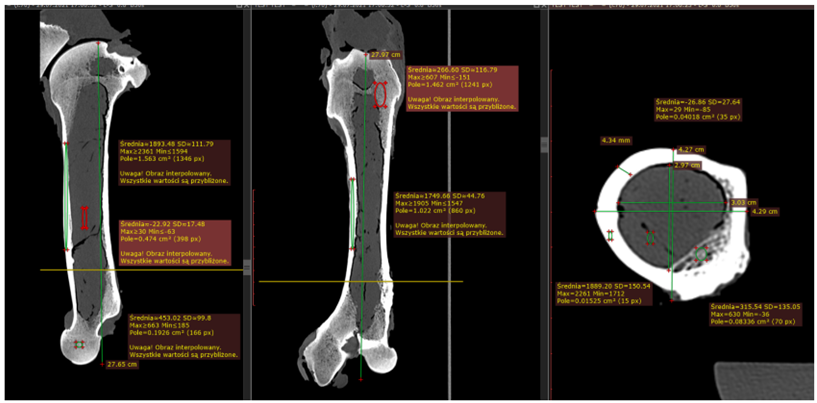

Korelacja wyników Ilościowej tomografii komputerowej (QCT) gęstości mineralnej kości zapisanych w skali Haunsfielda z modułem Younga będącym jednym z głównych parametrów opisujące własności mechaniczne kości.

Pomiary modułu Younga wykonane zostały za pomocą dwóch metod: maszyny wytrzymałościowej INSTRON oraz za pomocą metody bazującej na dyfrakcji światła. Pomiaru gęstości mineralnej kości dokonano za pomocą tomografu komputerowego z wzorcowym fantomem gęstości kości.